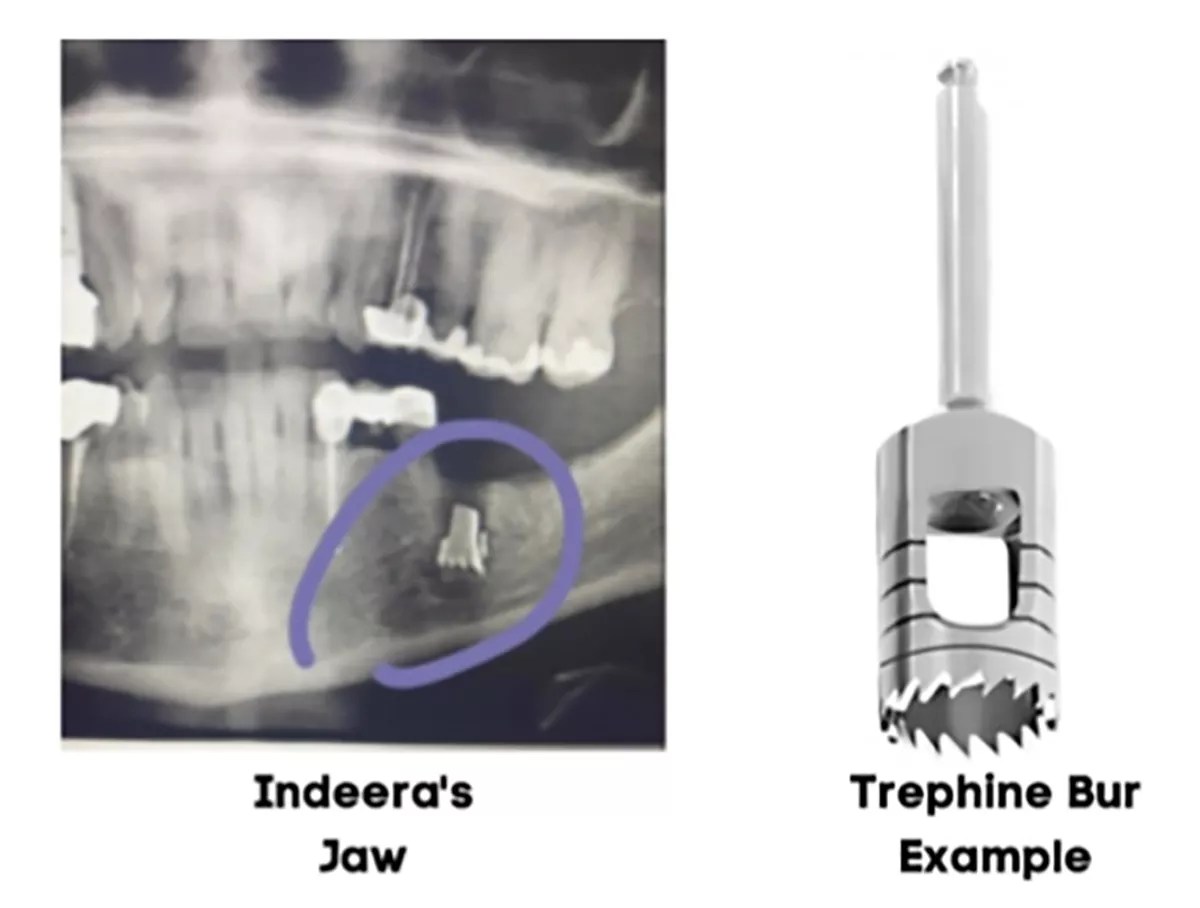

Months after undergoing dental surgery at Stonebriar Facial and Oral Surgery in Frisco, Indeera Musa claims X-rays revealed a piece of a drill bit used during the procedural was accidentally left inside her jaw, according to a lawsuit filed this year.

This is the kind of drill bit used in Indeera Musa's dental surgery last year. A piece of it was allegedly left in her jaw causing pain in the months after the surgery.

The surgery required Scott to use a drill bit called a trephine bur to remove the two faulty implants.

Usually, the stainless steel trephine bur is sunk over the failed implant and drilled into the jawbone. This creates a hole that allows the implant to be removed. Material is then grafted over the hole to prevent bone loss and preserve the area for future procedures.

When Musa returned in June, Scott did an X-ray on her jaw to see if it was ready for the new implants. The X-rays showed a dense metallic object in Musa’s jaw. Scott revealed that it was a broken piece of a drill bit he used during the surgery. He told Musa not to worry and likened “this conduct to leaving metal bullet fragments in a patient’s body,” according to the lawsuit.